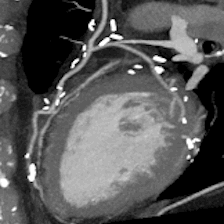

このボリュームCTにより早期発見から早期治療へつなげることが可能となり、心臓カテーテル検査の代替としても期待されます。

一部の症例以外では、従来の心臓カテーテル検査なしに血管狭窄の評価が可能であり、万が一、心筋梗塞になられた場合でも治療後の経過観察の心臓カテーテル検査は不要となります。